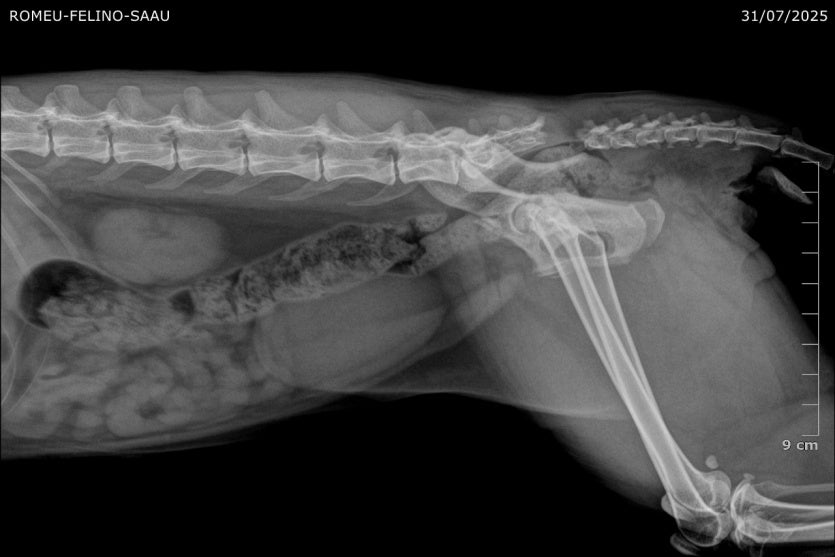

A Sociedade de Amparo aos Animais de Umuarama (Saau) iniciou uma vaquinha para custear a cirurgia de um gato atropelado no último dia 31. O acidente ocorreu na Rua Bahia, onde o animal mora com a tutora. O felino sofreu politraumatismo nas vértebras sacrais e lesões nos nervos. O impacto provocou danos graves na coluna, exigindo procedimento cirúrgico de alta complexidade.

A cirurgia foi realizada na última segunda-feira (4) pelo médico veterinário Matheus Pascotto. O procedimento não é coberto pelo orçamento da Saau, que depende de doações para manter o atendimento a animais em situação de risco.